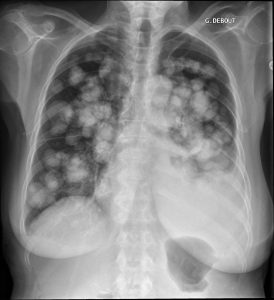

Image pulmonaire en « lâcher de ballons »

Mme B., 84 ans, est hospitalisée pour prise en charge d’une asthénie croissante associée à une dyspnée au moindre effort. Ses antécédents médicaux comprennent une hypertension artérielle